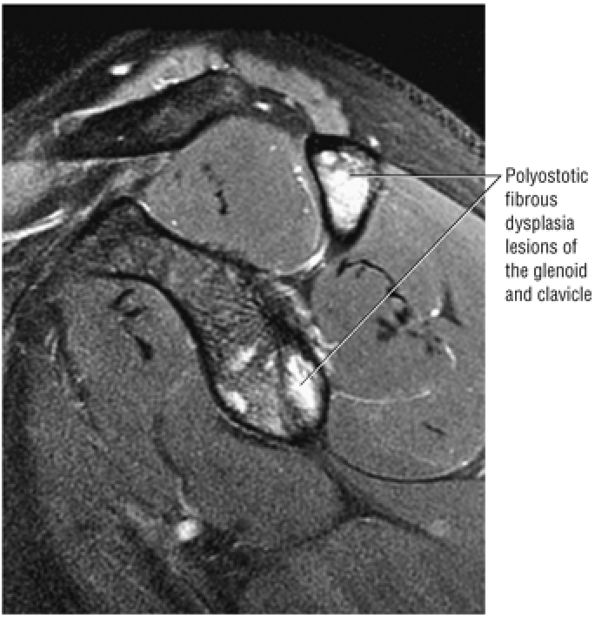

routine shoulder MR examination, when edema and hemorrhage are seen adjacent to the biceps tendon along the proximal humeral shaft. The large arc of muscle bundles making up the deltoid muscle are visualized on axial images anterior, lateral, and posterior to the humeral head and rotator cuff muscles.